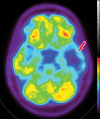

Neurodegenerative diseases are a devastating group of disorders that can be difficult to accurately diagnose. Although these disorders are difficult to manage owing to relatively limited treatment options, an early and correct diagnosis can help with managing symptoms and coping with the later stages of these disease processes. Both anatomic structural imaging and physiologic molecular imaging have evolved to a state in which these neurodegenerative processes can be identified relatively early with high accuracy. To determine the underlying disease, the radiologist should understand the different distributions and pathophysiologic processes involved. High-spatial-resolution MRI allows detection of subtle morphologic changes, as well as potential complications and alternate diagnoses, while molecular imaging allows visualization of altered function or abnormal increased or decreased concentration of disease-specific markers. These methodologies are complementary. Appropriate workup and interpretation of diagnostic studies require an integrated, multimodality, multidisciplinary approach. This article reviews the protocols and findings at MRI and nuclear medicine imaging, including with the use of flurodeoxyglucose, amyloid tracers, and dopaminergic transporter imaging (ioflupane). The pathophysiology of some of the major neurodegenerative processes and their clinical presentations are also reviewed; this information is critical to understand how these imaging modalities work, and it aids in the integration of clinical data to help synthesize a final diagnosis. Radiologists and nuclear medicine physicians aiming to include the evaluation of neurodegenerative diseases in their practice should be aware of and familiar with the multiple imaging modalities available and how using these modalities is essential in the multidisciplinary management of patients with neurodegenerative diseases.©RSNA, 2020.